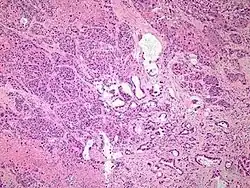

| Micrograph of an adenosquamous carcinoma of the lung. The adeno- or glandular component is on the left of the image and the squamous component on the right of the image. H&E stain. | |

Light microscopy shows a combination of gland-like cells and squamous epithelial cells.[4] On immunohistochemistry, it is typically positive for CK5/6, CK7 and p63, and negative for CK20, p16 and p53. On genetic testing, KRAS and p53 are typically altered.[4]